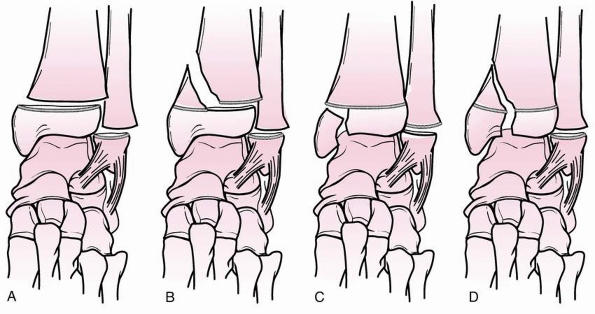

![]() |

FIGURE 26-3 Dias-Tachdjian classification of physeal injuries of the distal tibia and fibula.

|

-

Grade I: The adduction or inversion force

avulses the distal fibular epiphysis (Salter-Harris type I or II

fracture). Occasionally, the fracture is transepiphyseal; rarely, the

lateral ligaments fail. -

Grade II (Fig. 26-4):

Further inversion produces a tibial fracture, usually a Salter-Harris

type III or IV and rarely a Salter-Harris type I or II injury, or the

fracture passes through the medial malleolus below the physis (Fig. 26-5).

directly posteriorly, resulting in a Salter-Harris type I or II

fracture. Fibular fractures were not reported with this mechanism. The

tibial fracture may be is difficult to see on anteroposterior

radiographs (Fig 26-6).

Grade I: The external rotation force results in a Salter-Harris type II fracture of the distal tibia (Fig. 26-7).

The distal fragment is displaced posteriorly, as in a

supination-plantarflexion injury, but the Thurstan-Holland fragment is

visible on the anteroposterior radiographs, with the fracture line

extending

P.970proximally and medially. Occasionally, the distal tibial epiphysis is rotated but not displaced.

Grade II: With further external rotation,

a spiral fracture of the fibula is produced, running from

anteroinferior to posterosuperior (Fig. 26-8).